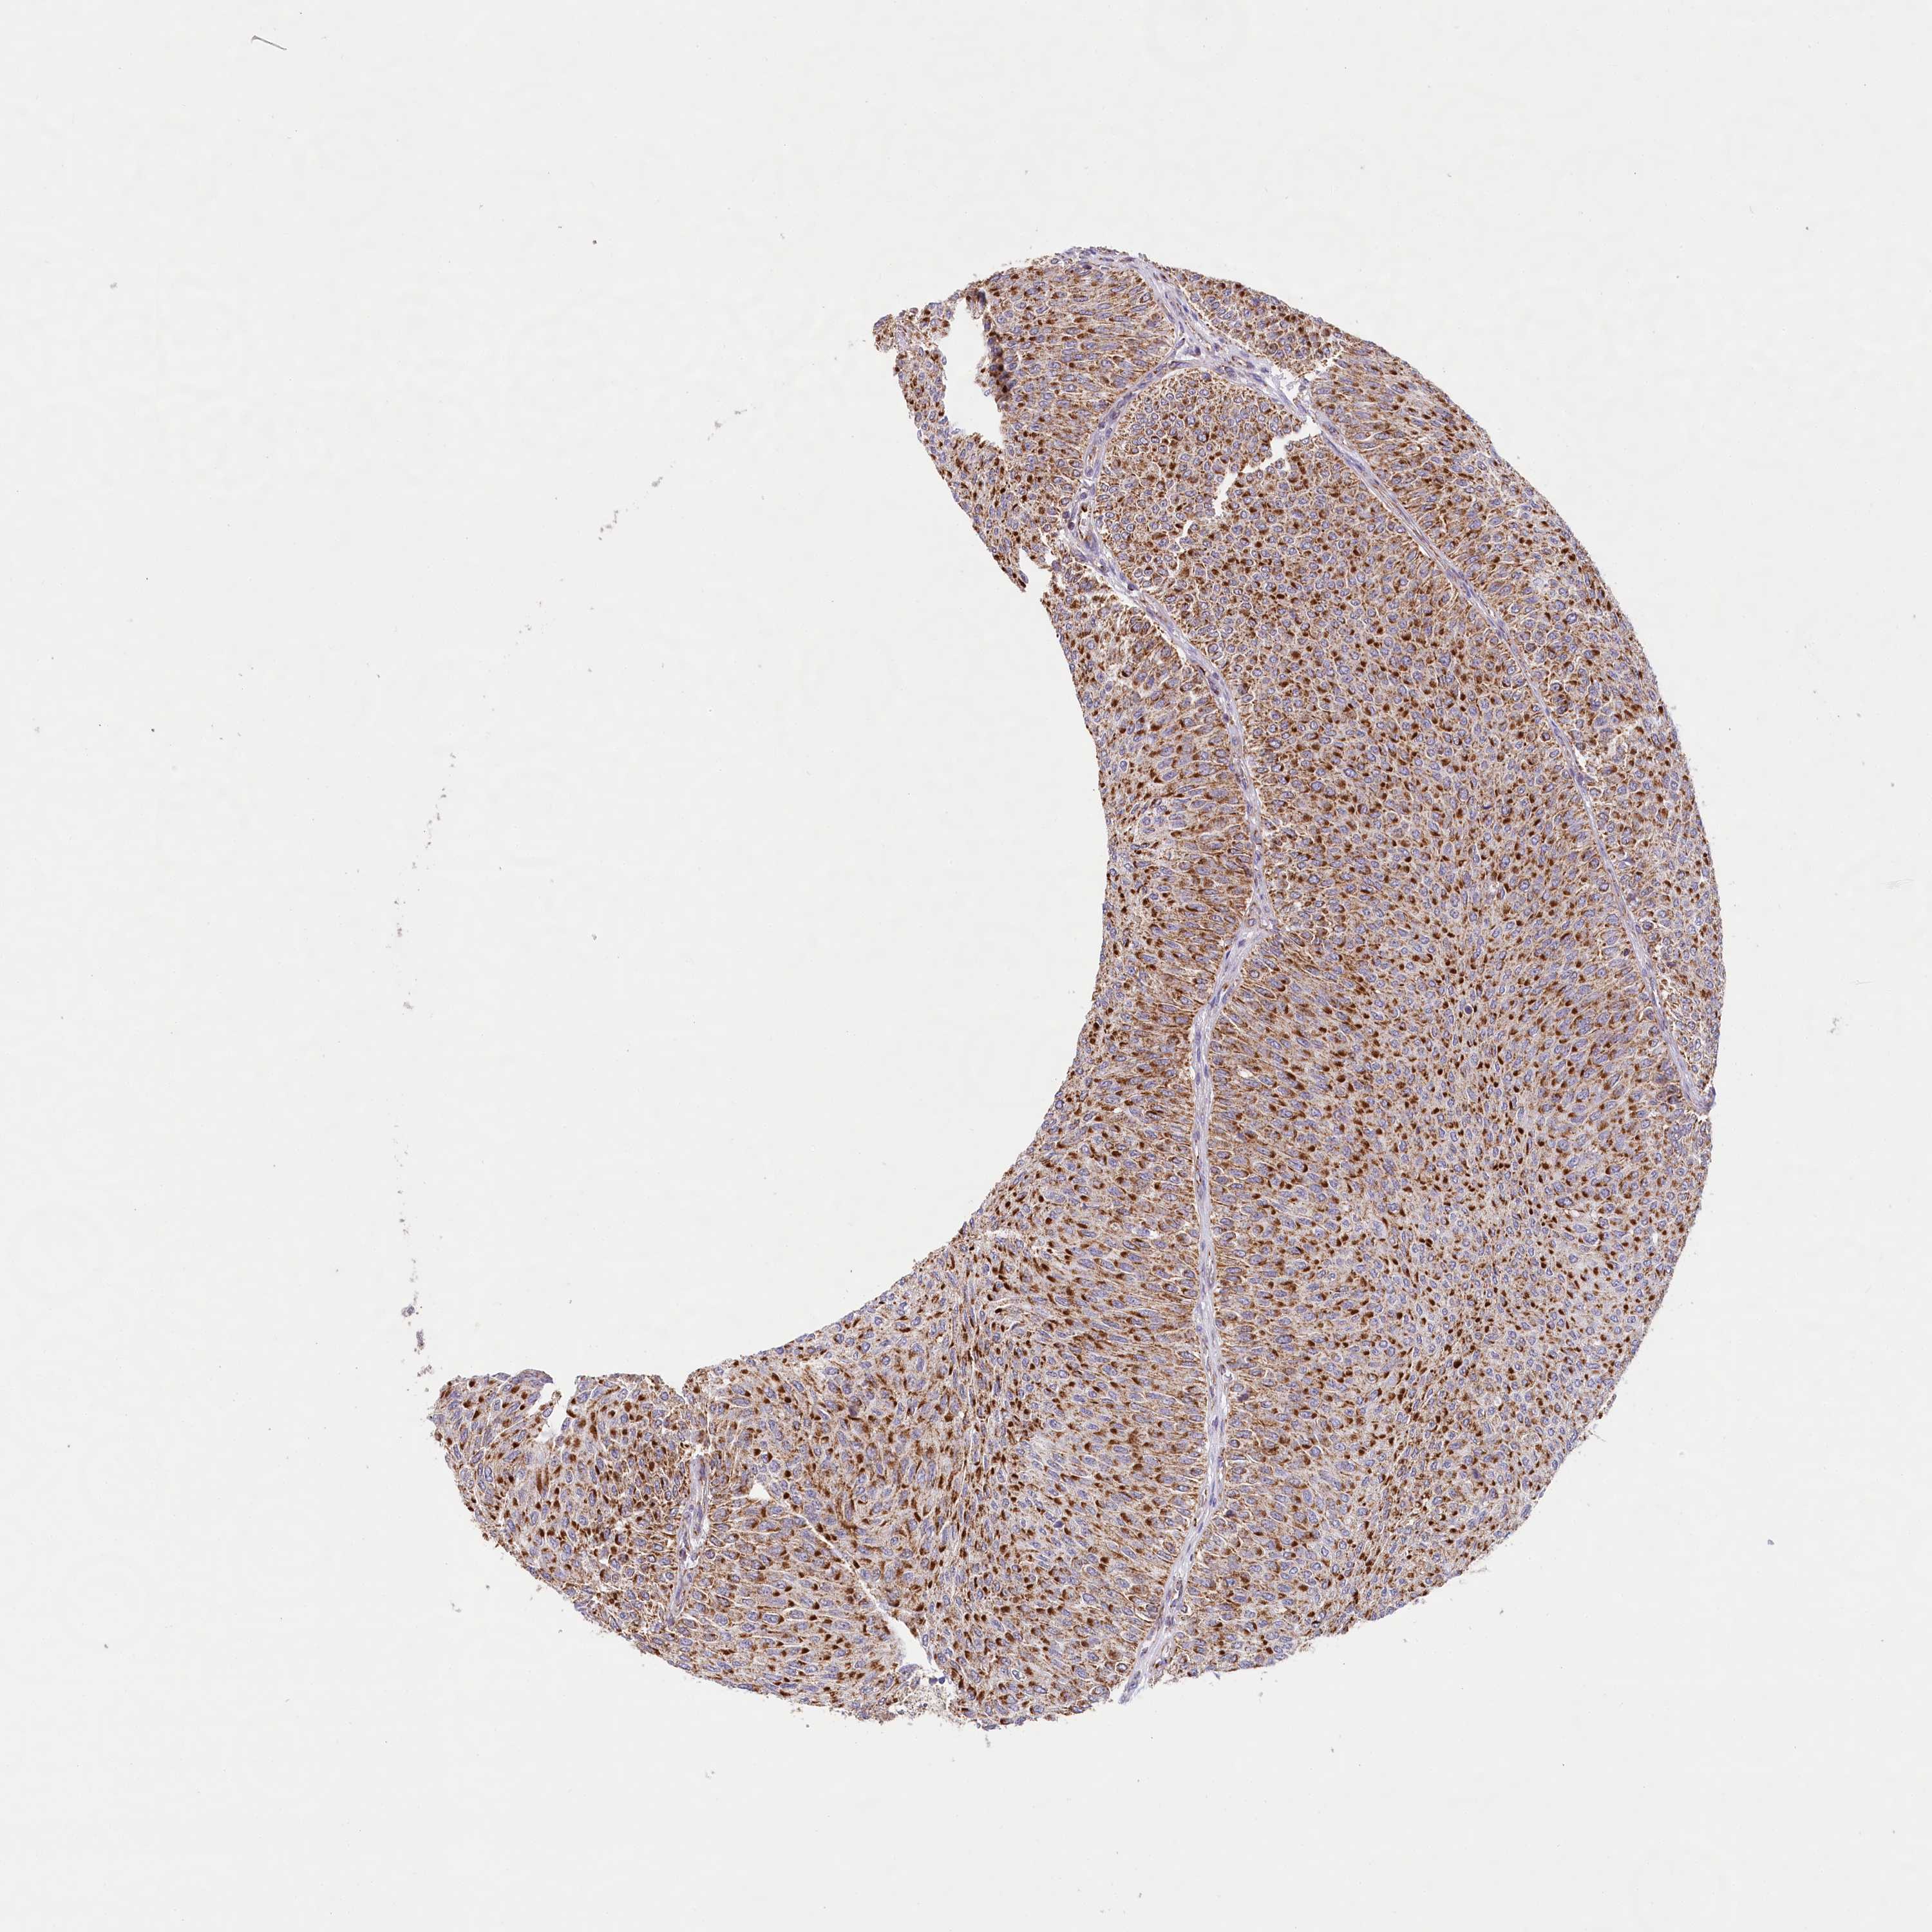

UROTHELIAL CANCER - Protein expressioni

A mouse-over function shows sample information and annotation data. Click on an image to view it in a full screen mode. Samples can be filtered based on level of antibody staining by selecting one or several of the following categories: high, medium, low and not detected. The assay and annotation is described here.

Note that samples used for immunohistochemistry by the Human Protein Atlas do not correspond to samples in the TCGA dataset.

Antibody stainingi

Antibody staining in the annotated cell types in the current human tissue is reported as not detected, low, medium, or high, based on conventional immunohistochemistry profiling in selected tissues. This score is based on the combination of the staining intensity and fraction of stained cells.

Each image is clickable and will lead to virtual microscopy that enables deeper exploration of all samples and also displays staining intensity scores, fraction scores and subcellular localization as well as patient and tissue information for each sample.

Antibody HPA032060

Antibody HPA032062

Antibody CAB034116

Location

Nuclear

Cytoplasmic/membranous

Cytoplasmic/membranous,nuclear

Urothelial carcinoma, Low grade

Urothelial carcinoma, High grade